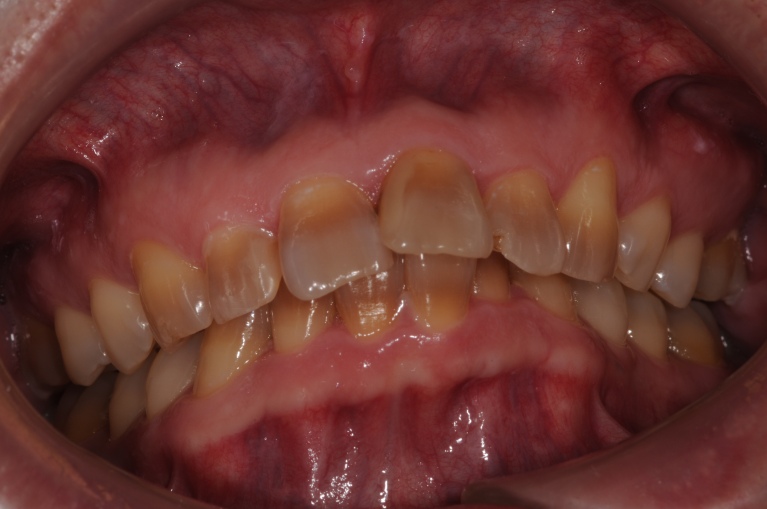

テトラサイクリン ※個人差があります。

施術前

施術後

(約6ヵ月後)来院回数6回